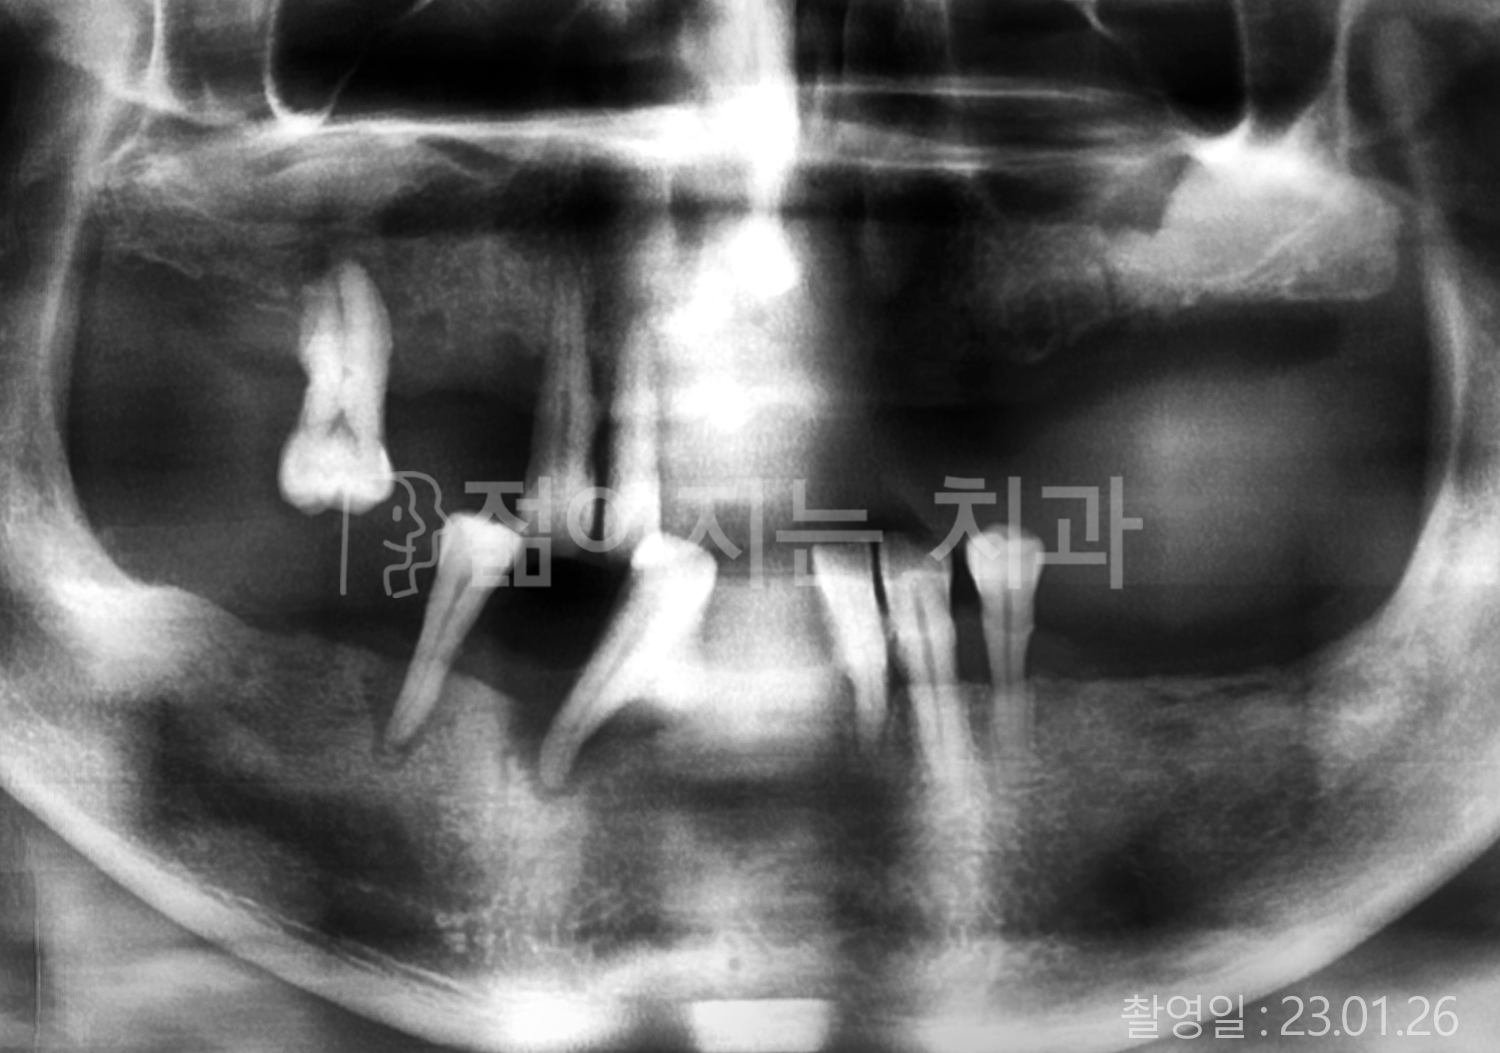

• 70대 고혈압, 고지혈증 전체치아 10개 이상 임플란트

• 60대 당뇨, 간염 전체치아 10개 이상 임플란트

• 80대 골다골증 전체치아 6개 이상 임플란트

• 70대 고혈압, 당뇨 전체치아 10개 이상 임플란트